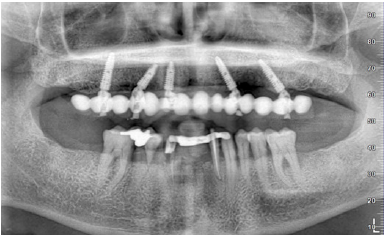

Figure 12: Post-surgical panoramic X-ray.

Figure 22: Post-surgical panoramic X-ray.